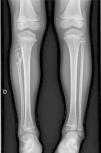

Posteriormente en la serie ósea completa, se comprobó la existencia de múltiples lesiones metafisodiafisarias con trabeculación y patrón escleroso en hemicuerpo derecho (fig. 2).